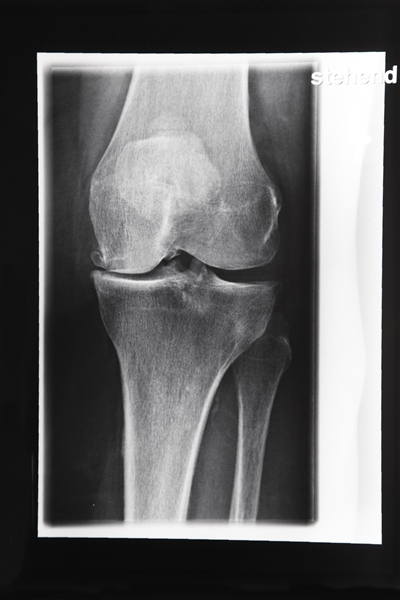

Arthrose im Kniegelenk: vielfältige Ursachen wie Übergewicht / falsche Ernährung, aber auch genetische Veranlagung | Foto: colourbox.com

Degenerative Veränderungen des Gelenkknorpels am Knie: 2/3 der über 60-Jährigen sind davon betroffen.